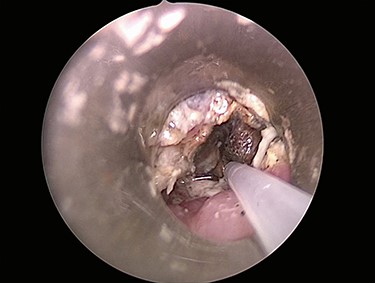

Six days later, repeat endoscopy was performed. A 1-cm area consistent with a broncho-esophageal fistula was seen on the posterior wall of the right mainstem bronchus just past the carina (Fig. 3A). Esophagram also clearly showed the fistula (Fig. 3B). A 10 French fenestrated nasogastric tube was placed such that the fenestrations were both above and below the fistula. Feeding jejunostomy tube was also surgically placed. The patient tolerated the procedure well and was able to transition to full feeds.

(A) Repeat bronchoscopy shows a broncho-esophageal fistula on the posterior wall of the right mainstem bronchus just past the carina. (B) Esophagram was performed while in the operating room and clearly shows the fistula to the right mainstem.